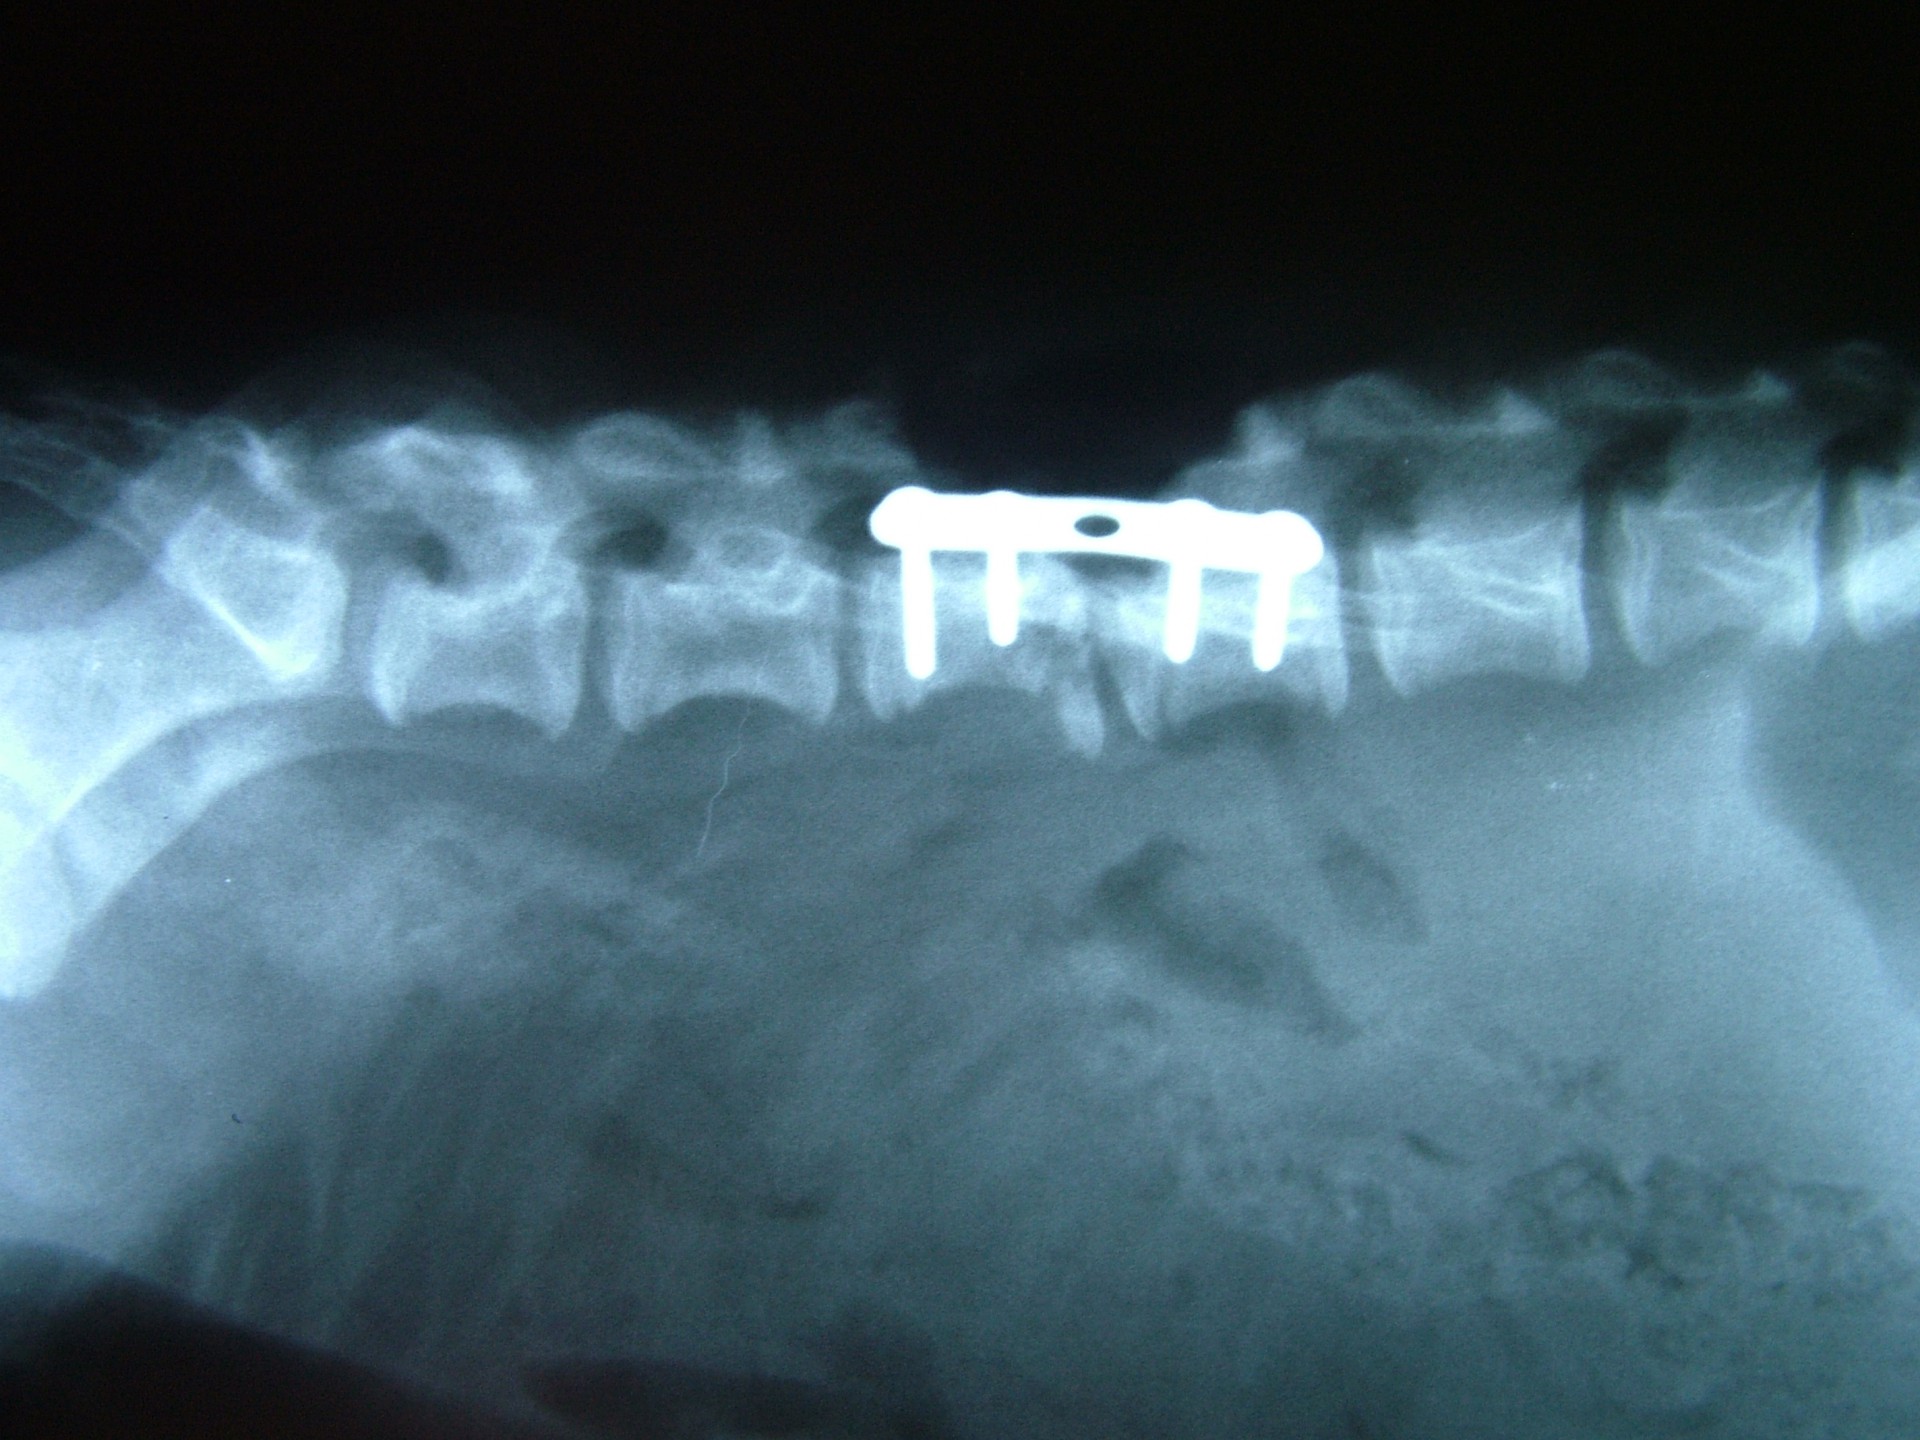

A törött csigolyatestek adaptációja és rögzítése a nyitott gerinccsatorna mellett komoly kihívást jelent. A későbbi elmozdulás elkerülésére többféle műtéttechnika alkalmazható, melyek közül a csigolyatestek lemezes osteosynthesise ill a fixateur interna használata terjedt el leginkább. Első esetben a sérülés előtti és mögötti csigolyákat lemez és csavarok segítségével egymáshoz rögzítjük, míg az utóbbi esetben a törés előtti és mögötti egy vagy több csigolyatestet két oldalról behelyezett csavarok és egy steril kétkomponensű akrilát műgyanta segítségével rögzítjük.

Szerencsés esetben az állat a műtétet követően néhány héten belül, akár tünetmentesen gyógyul. Az implantátumok későbbi eltávolítására - amennyiben szövődmény nem alakul ki - általában nincs szükség.

Bármilyen műtét után kialakulhat olyan szövődmény, mely gennykeltő baktériumok műtéti sebben történő elszaporodásával jár (szeptikus szövődmény). Különösen igaz ez olyan beavatkozásokra, amikor valamilyen idegen anyag (implantatum) kerül a szervezetbe beültetésre. Ilyen idegen anyag a gerinctörés műtéteknél használatos fixateur interna rögzítőanyaga (akrilát műgyanta) is. Abban az esetben, amikor a szeptikus szövődmény antibiotikumok célzott adásával nem gyógyítható, a test számára idegen anyagot el kell távolítanunk. A gerinctörés műtéténél ez a nyitott gerinccsatorna miatt fokozott kockázatot jelent. Az implantatum eltávolítását követően azonban a szeptikus folyamat gyógyul és a helyén kialakuló kötőszövet a fixateur externának megfelelően rögzíti a gyógyulófélben lévő csigolyát is.